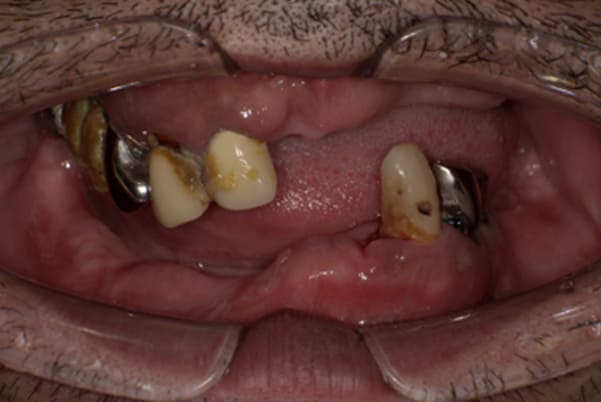

上前歯はブリッジの差し歯により根が折れ炎症を起こしお痛みのある状態でした。

原因は長期使用により下の義歯の歯が削れたことにより、下前歯が上前歯を突き上げ強い力が加わっていたことが根本的な原因と考えられます。

治療前は、奥歯が下がり、かみ合わせが乱れています。適切な入れ歯はそのままのかみ合わせで義歯を作るのではなく治療後のように、前歯から奥歯までのラインが真っすぐ揃った、かみ合わせの面を適切に付与し、よく咬め、残りの歯に負担がかからないかみ合わせとしました。

とにかく何も食べられないこと、人に会えないことから、なるべく早く何とかしたいとのご希望でした。

患者様とご相談の上、まず早急に上記を回復させるため、初診含め3度の来院でお食事ができ、見た目を回復できるように治療用義歯を作製、装着しました。

本来は、数本の上前歯の折れてしまって残せない歯は抜いてから歯肉の治癒を待ち、数か月後に型どりから作製になりますが、抜歯即時義歯といって、歯を抜く前に型、かみ合わせをとり、抜歯を行ったその日に上下の義歯を装着する特殊な治療法を用いたことで、10日後には治療用義歯をお口に装着することができ、お痛みもなくお食事ができ、ご友人とのお食事にも行けることが可能になりました。

本来、入れ歯作製は技工所と言って、義歯を作製する所に発送するため、作製には時間がかかりますが、院内に技工専用スペースを完備しており、長年、義歯治療において、技工も技術の習得してきましたので技工士さんではなく、かみ合わせの道具も私自身で院内で作製したことで、初診日の次の日にご来院いただきかみ合わせを採ることで、診断、型どり、かみ合わせ、装着まで10日という最短のご希望にこたえらた方です。

上顎治療前

-

上顎治療後

根のみの7本は虫歯にもなっており歯肉は腫れあがっています。

残りの歯もレントゲンで重度の歯周炎によりぐらぐらな状態でした。